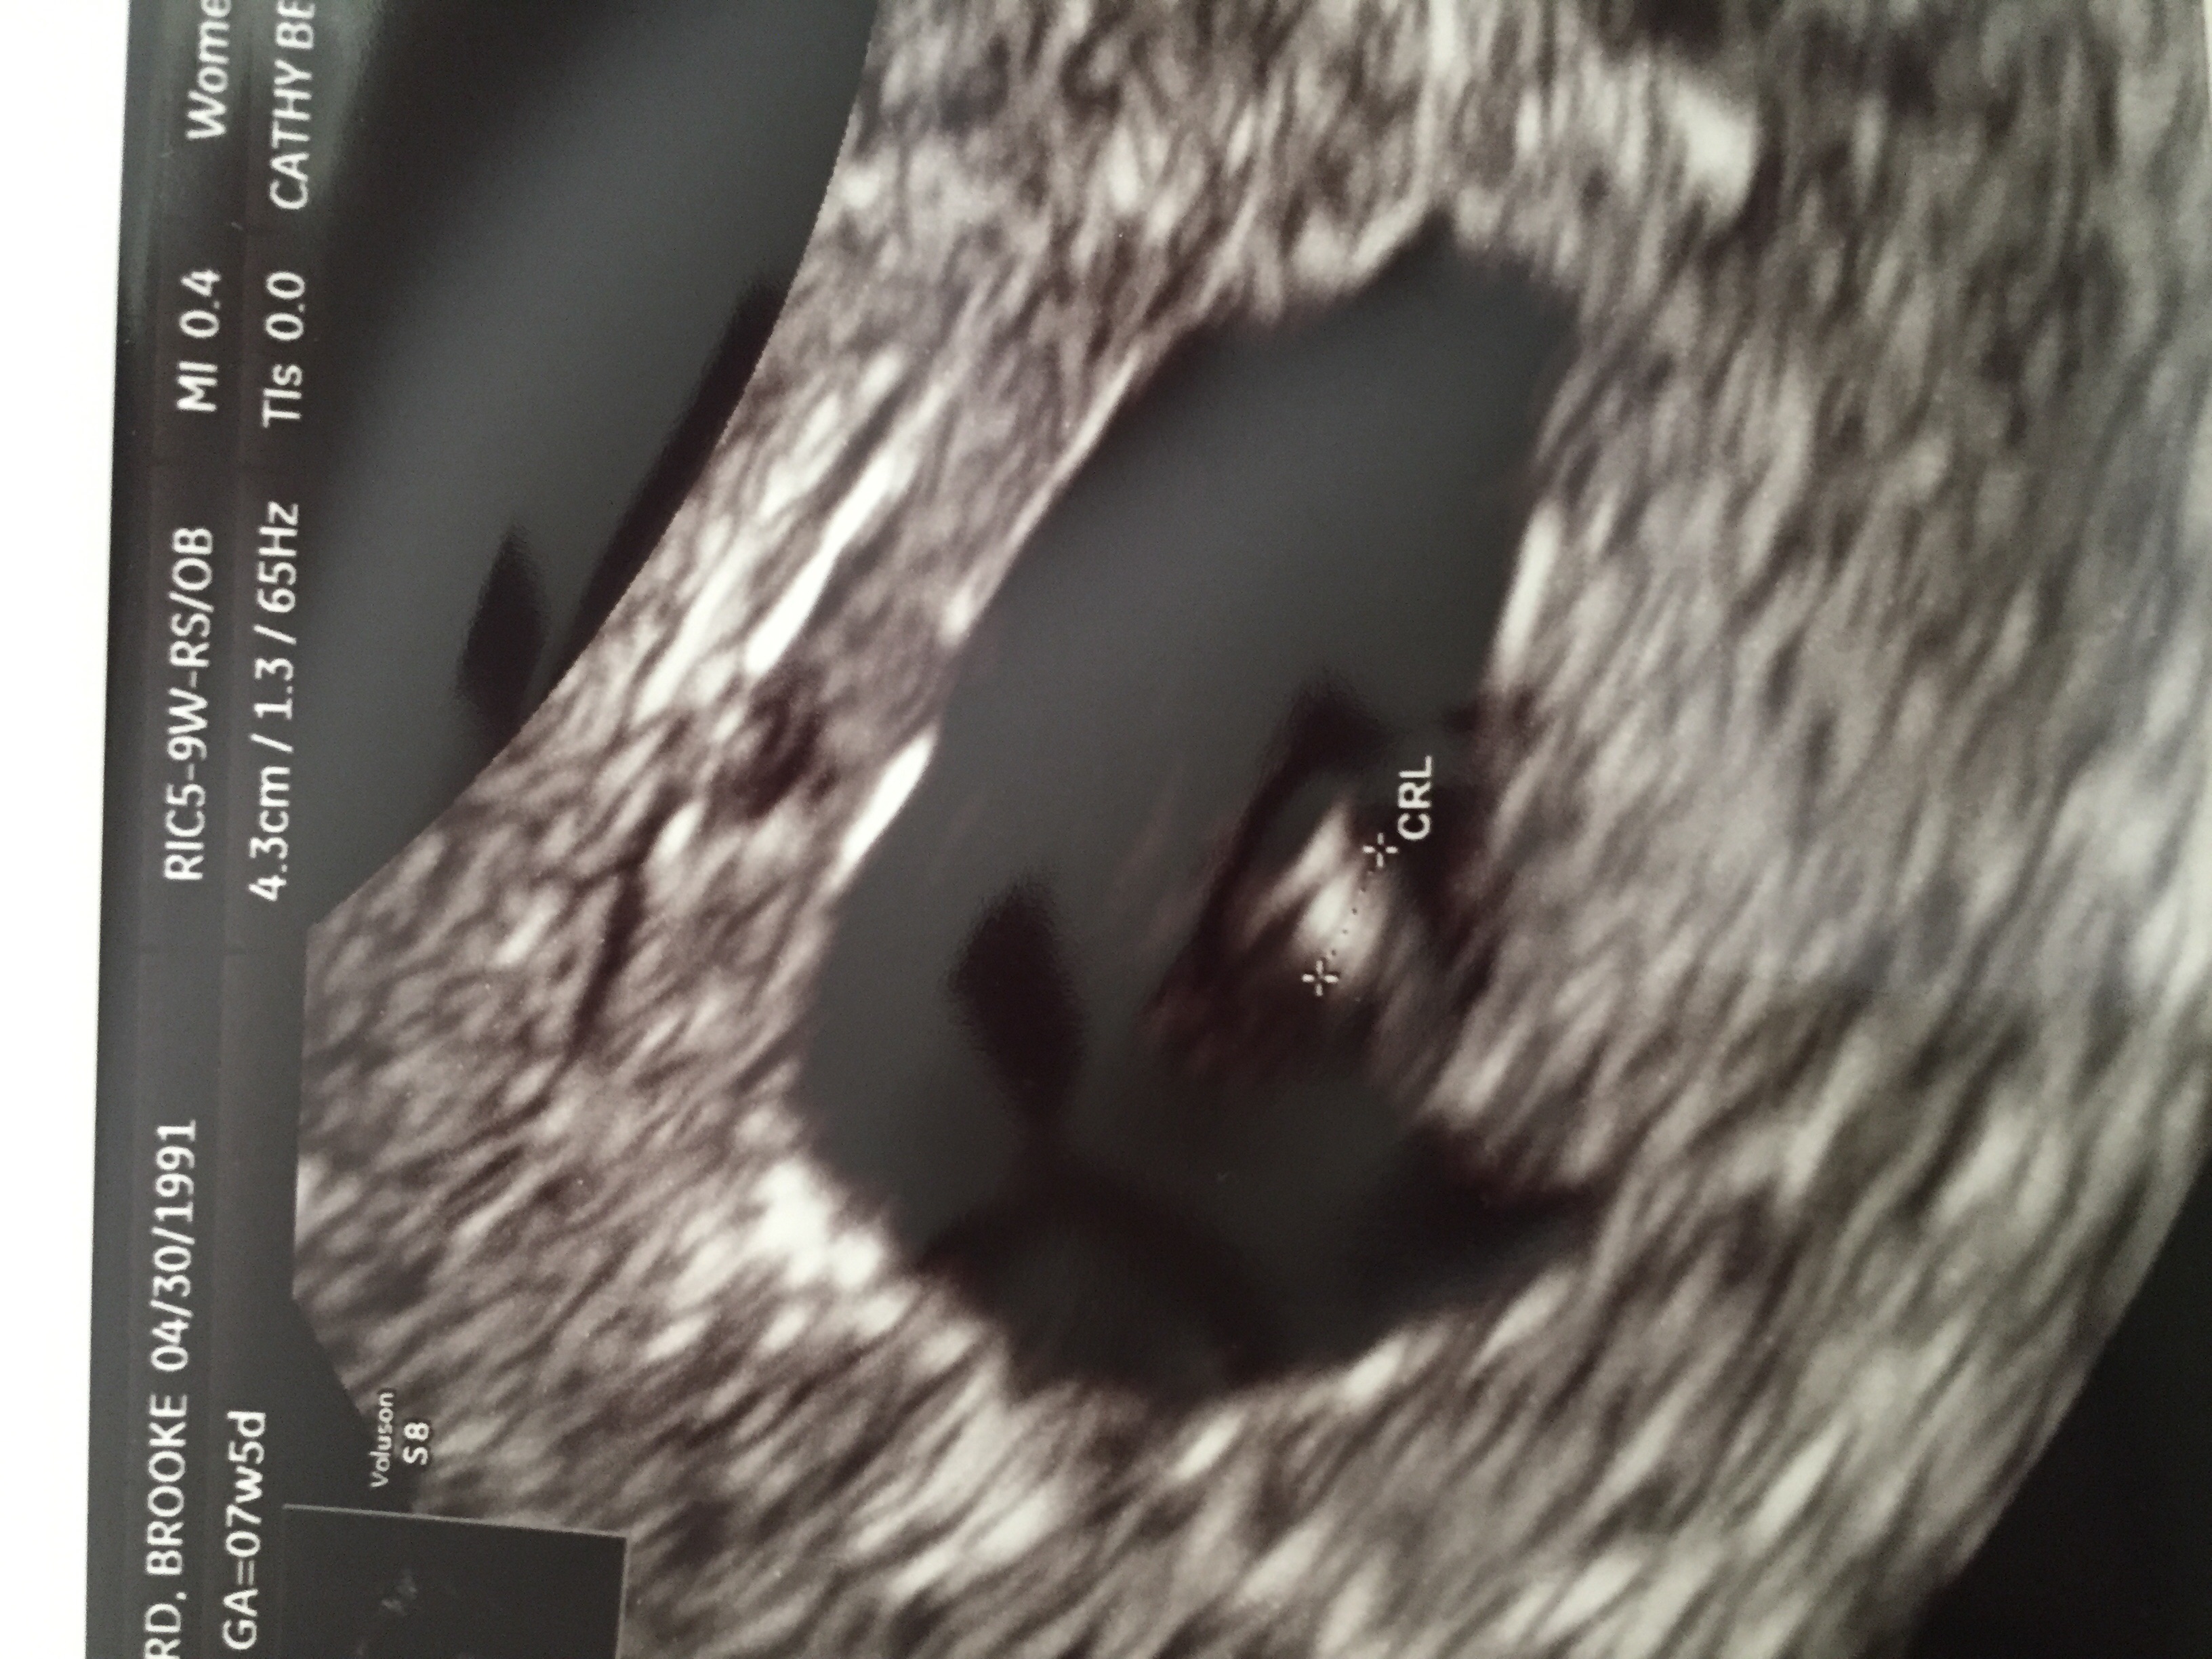

does anyone know how true the Ramzi theory is?? This was my vaginal ultrasound at 5w5d. I'm currently 11w. My doctor does not to the blood work to determine the gender so I'm having to wait til LATE August and it's driving me nuts!!

I say boy it looks like your baby is more to the right side and the placenta as well. Remember you would place this ultrasound on top of your tummy to know which side is left and which is right. Ramzi was correct for me my baby was on the left and she's a girl

ABDOMINAL- FLIP IT... It's the opposite so this is really the right... Boys are on the right